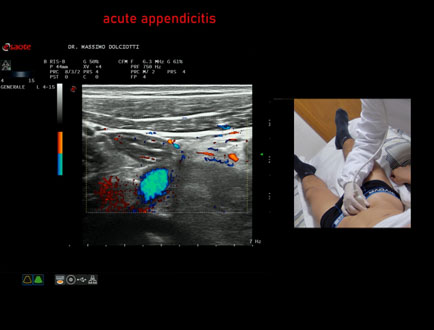

Data inserimento: 20/02/2026

Ecografia del: 13/02/2026

Strumento: Esaote MyLab Eight

Sonda: Lineare Multifrequenza 4-15 MHz

Età Paziente: M 22 anni

Motivazione dell'esame: da un giorno dolori addominali in sede ileo-cecale.

Commento all'esame: le immagini ed il video documentano, in sede ileo-cecale, appendice di spessore aumentato (9 - 10 mm - V.N. inferiore a 6 mm) con incremento della vascolarizzazione. Gli elementi ecografici segnalati orientano per appendicite acuta.

Conclusioni: appendicite acuta (acute appendicitis).

In collaborazione: Dr.ssa Marica Manfredi - Ancona, Dr. Ilir Qose - Ancona

Presentazione: Dr. Massimo Dolciotti - Ancona